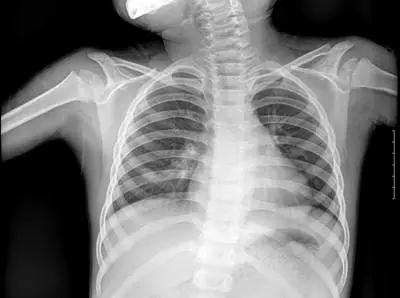

X光:主要看“密度” 擅長骨折、肺臟病變

X線是一種能量很大的電磁波,對人體組織結構有著很強的穿透力。但人體各組織結構的密度不同,X線穿透時被吸收的量不同,就形成了黑白灰分明、層次顯著的“片子”。

▲X射線成像圖

骨骼、鈣化灶、體內液體等(聽起來質地較厚重的組織),吸收X光較多,因此形成白色影像,也就是傳說中的“高密度影”,上圖的上臂、肋骨就是如此。呼吸道、胃腸道、脂肪組織(聽起來質地較疏松),吸收X光較少,在片子上呈現黑色影像,即“低密度影”,圖中含氣體較多的肺臟是代表。再就是密度居中的實質器官、肌肉、結締組織,比如心臟,在片子上呈現的影像介于黑白兩色之間。X光片“涇渭分明”的特點幫醫生辨別身體的不同病變。骨折、肋骨病變,密度高的骨骼白色影像哪里出問題一目了然,比如液氣胸等肺部及氣道病變,肺臟的黑色影像中就會混入明亮的白色。

不過,X光檢查也有弱點,那就是缺乏特異性,比如照完X光發現肺部有陰影,可這個陰影到底是啥原因導致的呢?是肺結核?是普通炎癥?還是腫瘤?這時候,就該先讓CT出場了。